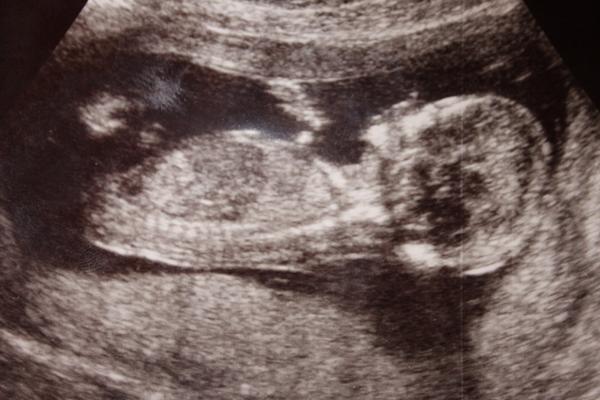

Ahojky holky. Co myslíte u nás? Co to bude? Foto je z 17.týdne 🙂

@snezenka123 - těžko říct....odhaduju kluka spíš.......Ale mě v 17tt řekl kluka a na dvou velkých UTZ potvrdili holčičku 🙂

holky , tak jsem asi mela pravdu -- pokud výběžek, ze kterého bude casem pohlavni organ miri nahoru, bude to kluk, pokud dopředu, bude to holka. tedy u nas to vyslo -- pridavam fotku, dle které jsem to odhadovala jiz ve 13. tydnu -- a tedy je ze screeningu -- jde o prurez miminkem nikoli o foto jen z boku. .